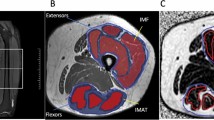

Single cross-sectional CT

Using a CT scan (Somaton Plus; Siemens, Sorheim, Germany), participants were assessed in supine position with arms extended above their head. A single cross-sectional CT at the L4-L5 intervertebral space image was acquired to measure the VAT area. The boundary between VAT and abdominal subcutaneous adipose tissue was defined using the abdominal and oblique muscles in continuity with the deep fascia of the paraspinal muscles and the anterior aspect of the vertebral body33. Cross-sectional CT thigh images were also obtained using contiguous 7-mm–thick cross-sectional images of both legs obtained between the inferior ischial tuberosity and the superior border of the patella. The IMAT region was measured between muscle groups and underneath the fascia. The IMAT volume (cubic centimeters) identified in each image was calculated by multiplying the image thickness (7 mm) by the tissue area (square centimeters), and IMAT volume (litters) was then converted to mass units (kilograms) multiplying the volume by the assumed constant of fat density (0.92 kg/L)34.

All images were obtained using 120 kVp, 480 mA, and 512 × 512 matrix with a 48-cm field of view. CT data were analysed by specific software (Slice-O-matic, Version 4.2, Tomovision,Montreal, Canada) based on image morphology. A combination of watershed techniques and edge detection filters was employed. Different tissues were identified using boundaries in Hounsfield Units (HU) set to −29 to +150 for muscle, −190 to −30 for IMAT and subcutaneous adipose tissue, and −150 to −50 for VAT35.